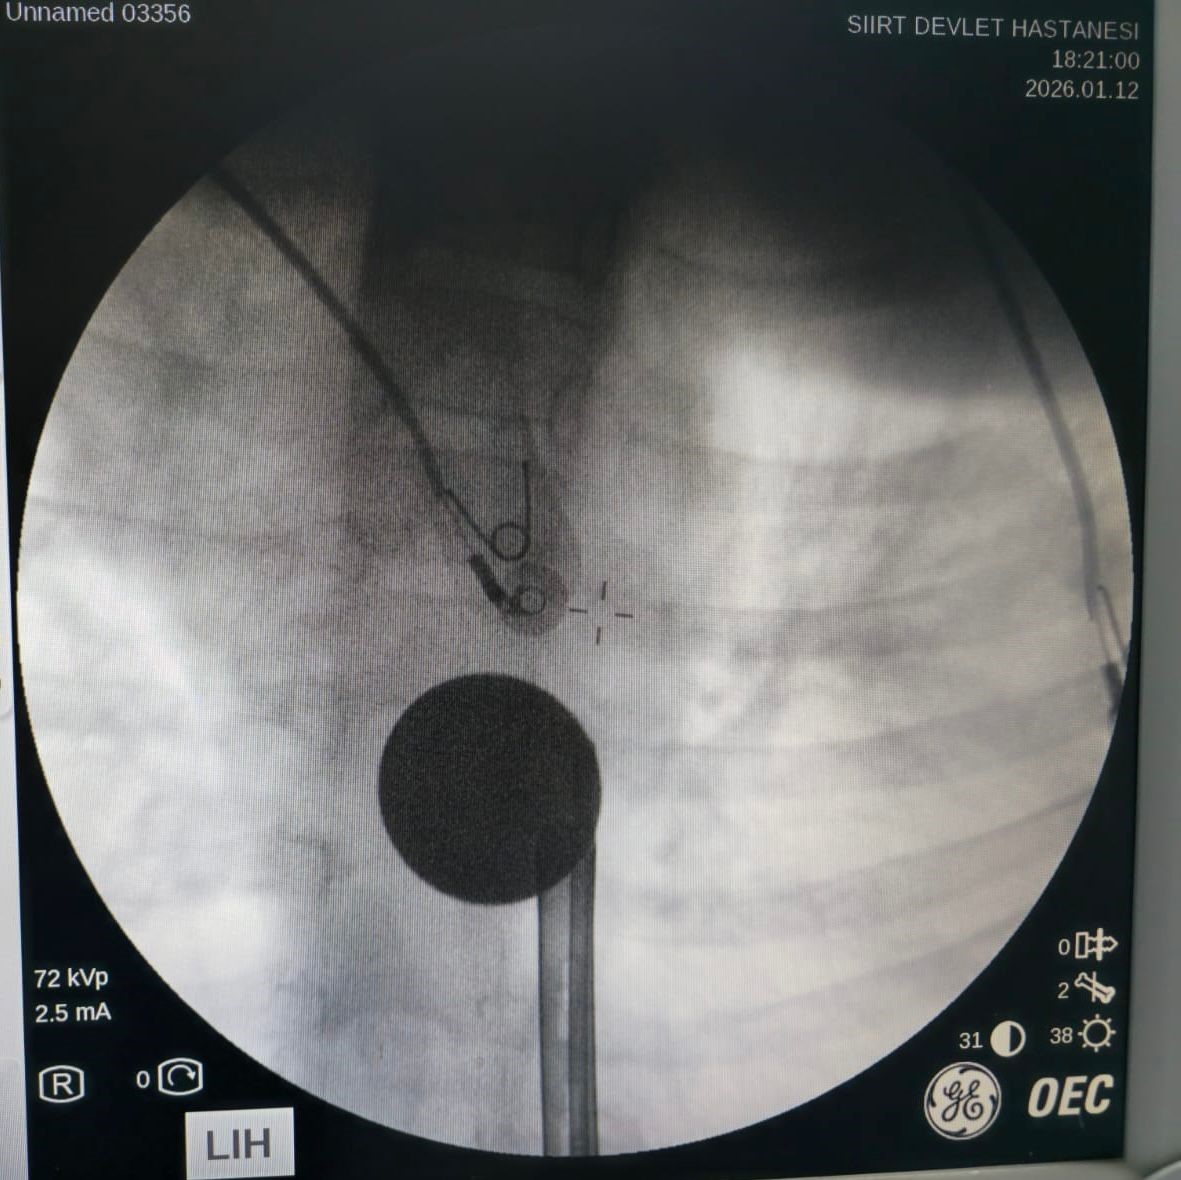

Yabancı cisim yutma şikayetiyle ailesi tarafından Siirt Eğitim ve Araştırma Hastanesine getirilen 8 yaşındaki Y.K., yapılan ilk değerlendirme ve görüntüleme tetkiklerinin ardından ilgili branşlarca operasyona alındı. Y.K.’nın yemek borusuna kadar ilerlediği tespit edilen madeni para, gastroenteroloji uzmanı Dr. Yaren Dirik ve kulak burun boğaz hekimi Yasin Gökçınar tarafından müdahale edilerek çıkartıldı. Operasyonun ardından bir süre gözlem altında tutulan Y.K., tedavisinin tamamlanmasıyla taburcu edildi.

Siirt Eğitim ve Araştırma Hastanesi Başhekim Yardımcısı Uzman Dr. Burak Özkan, çocuk hastalarda yabancı cisim yutma vakalarının ciddi riskler oluşturabileceğini söyledi. Uzm. Dr. Özkan, "Hastanemize başvuran 8 yaşındaki hastamızın yemek borusuna kaçan madeni para, gastroenteroloji ve KBB ekiplerimizin koordineli ve titiz çalışmasıyla herhangi bir komplikasyona yol açmadan başarılı bir şekilde çıkarılmıştır. Operasyon süreci sorunsuz geçmiş olup hastamızın genel durumu iyidir" dedi.